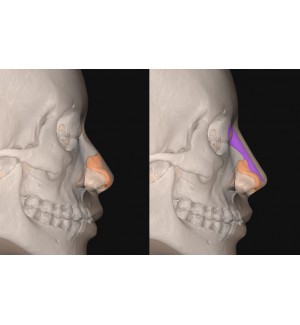

Nền tảng phần mềm hình ảnh y tế cho phẫu thuật thẩm mỹ cung cấp các giải pháp cấy ghép tùy chỉnh cá nhân hóa .

Trước khi tiến hành phẫu thuật, nhân viên y tế có thể phân tích thông tin bệnh nhân thông qua phân tích tự động AI, thiết lập kế hoạch phẫu thuật, thiết kế cấy ghép và dự đoán phẫu thuật sau phẫu thuật.

Chương trình dành riêng cho thiết kế FITme:

Mô phòng hình ảnh thực tế của công nghệ FITme: